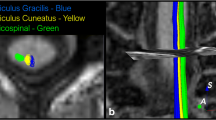

The corticospinal tract (CST), arcuate fasciculus (AF) and its long segment (AFl) were reconstructed in 17 healthy subjects imaged twice using a deterministic approach. Coefficients of variation (CVs) of diffusion-derived tract values were used to assess the microstructural reproducibility. Spatial correlation and fibre overlap were used to assess the architectural reproducibility.

Next, the CST, the AF and AFl were extracted for each individual from regions of interest (ROIs) according to a priori information of tract location [50, 51]. The tracts of interest were only delineated in the left hemisphere considering the left hemisphere lateralisation of these tracts when subjects are strongly right-handed [52, 53]. The ROI sets of all tracts of interest were manually placed only by the first author (G.K.) as a previous study reported a high interobserver reliability in tract-specific analysis [54]. This was done following the guidelines and protocols described in previous studies, where figures showing the ROI placement are also present [9, 32, 33, 51]. The CST was extracted by placing two ROIs on axial slices. The first ROI included the cerebral peduncle at the level of the decussation of the superior cerebellar peduncle. The second ROI was drawn right after the bifurcation to the motor and sensory cortex to include only primary motor cortex, and not sensory tracts [51]. The AF was extracted by placing two ROIs on coronal slices. The first ROI was selected where the AF, appearing as a green triangular shape on coronal images (indicating anterior/posterior orientation), was seen to be largest. The second ROI was selected at the level of the splenium of the corpus callosum, where the AF makes a sharp turn towards the temporal lobe [9, 32]. The AFl was defined by using the first ROI used for the delineation of the AF, and by placing a second ROI on an axial slice through which the AF passes in the superior/inferior direction [33].